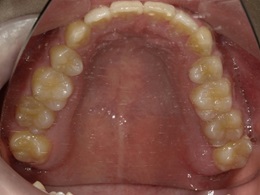

上顎治療前

治療前下顎